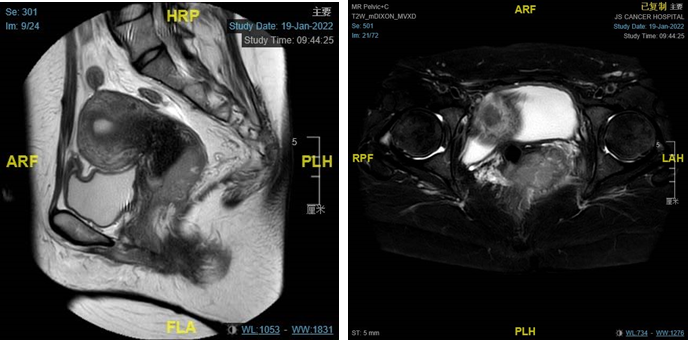

盆腔MRI检查:阴道后壁肿瘤约4.6*1.6*4.7cm,病灶与宫颈后唇分界不清,局部与直肠前壁分界不清。肿块最外缘距左侧盆壁约2cm,下缘距阴道外口约2.9cm,增强后明显强化。

图2. 盆腔MRI提示阴道后壁肿瘤约4.6*1.6*4.7cm,病灶与宫颈后唇分界不清,局部与直肠前壁分界不清

MRI检查:阴道后壁肿瘤变大,且与肛提肌分界欠清,考虑为引起下腹疼痛的原因。

图5. MRI提示阴道后壁肿瘤变大,且与肛提肌分界欠清